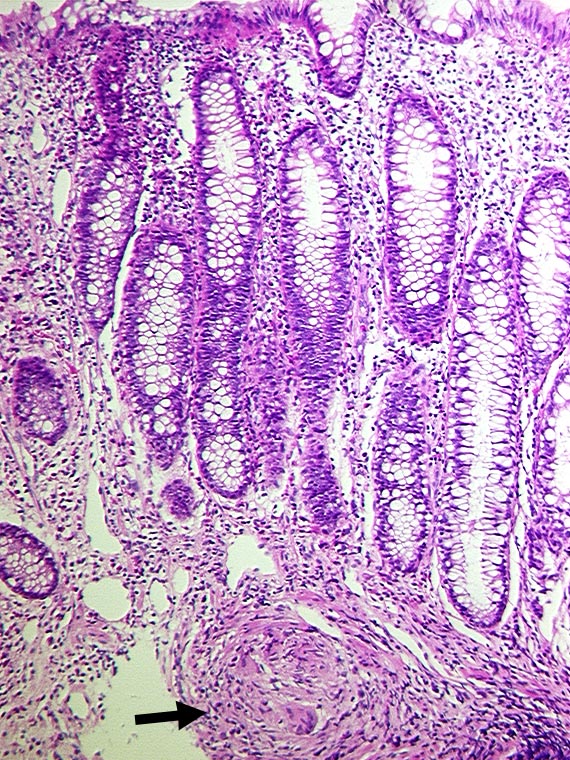

PathoPic ID 1133 - Granulom in der Submukosa bei Morbus Crohn

Granulom in der Submukosa bei Morbus Crohn

An dieser Stelle weitgehend unauffällige Mukosa. In der Submukosa ein epitheloidzelliges

Granulom mit einer Riesenzelle.

Fokal aktive Entzündung.

Bekannter Morbus Crohn seit 8 Jahren.